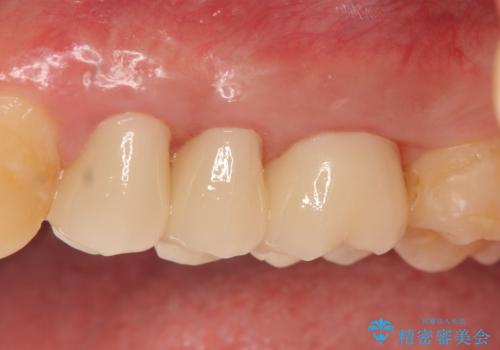

その後歯茎の回復を待つ間に再根管治療を行い、歯茎の回復後オールセラミッククラウンにて補綴を行いました。

今回用いたオールセラミッククラウンはジルコニアフレームという白い素材の上にセラミックを盛っているため、審美性が非常に高いのが特徴です。

また、ジルコニアは人工ダイヤモンドの材料にも使われているほど高い強度を持っており、そのためオールセラミッククラウンは審美性だけでなく、奥歯やブリッジの補綴も可能とするクラウンです。